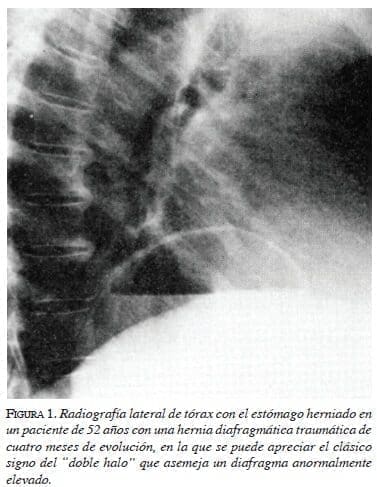

En el hemitórax derecho se puede observar desviación del mediastino hacia ese lado3,4,18-20. El pulmón izquierdo se puede observar colapsado6. Puede identificarse un neumotórax cuando el estómago está perforado14. El hemidiafragma izquierdo se encuentra muy elevado y no se observa la burbuja gástrica por debajo del diafragma3,5,6,20. Ocasionalmente, se puede ver un nivel hidroaéreo en el estómago herniado1,4,5,9,10, el que puede confundirse con un quiste hidatídico o un absceso pulmonar (figura 1). Con mayor frecuencia aún, es posible identificar el estómago dentro del tórax (figura 2). Estas alteraciones se pueden asociar a derrame pleural izquierdo6,18,19. La instalación de una sonda nasogástrica puede demostrar la presencia del estómago dentro del tórax hasta en 95 % de los casos y, además, contribuye a descomprimir el estómago y aliviar la presión intrapleural6,8,10,17.